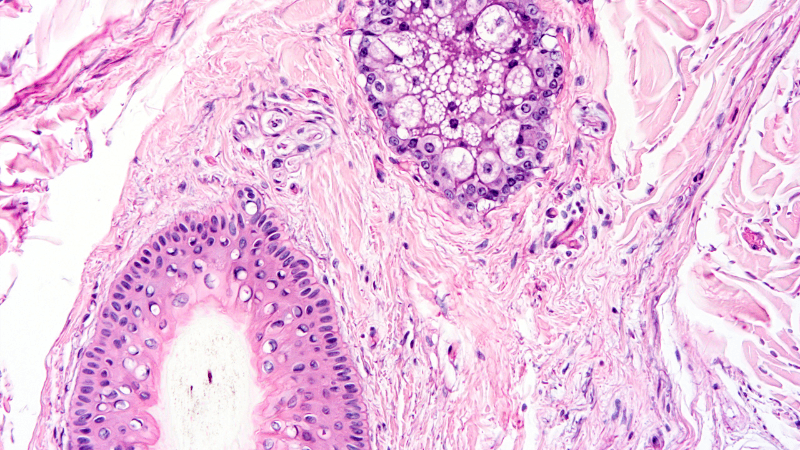

Scientists have found a way to rebuild organs in the laboratory starting from the backbone of the organ itself. However, to do so, researchers had to find a way to remove all the blood and cells that the organ was made of. This process is called “decellularization”. The process is very visual: the organ, usually a pink/reddish colour and dense, gradually becomes white and translucent. What is left, is the natural skeleton of the organ, a mesh of protein of the Extracellular Matrix (also called ECM). By decellularizing organs, the scientists have obtained 3D scaffolds which have the shape, the structure, and the same components as the organ of origin. This has many advantages because cells seeded (injected or placed inside the scaffold) will find an environment, composed by the ECM, which really resemble the tissues of origin. This helps the cells to get well acquainted, to “get cosy” and to perform the function they have in the organ.